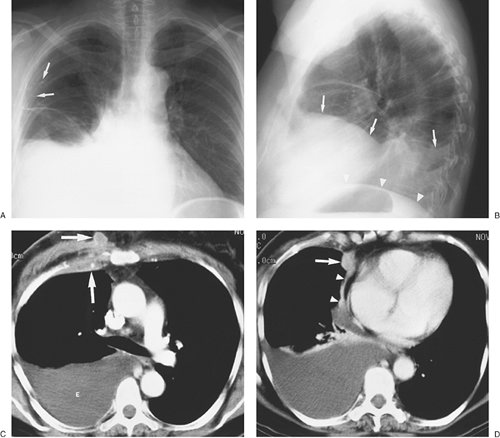

FIGURE 9-11. Malignant pleural effusion. A: PA chest radiograph of a 62-year-old woman with metastatic breast cancer who has had a right mastectomy and axillary node dissection (note surgical clips in right axilla; arrows) shows apparent elevation of the right hemidiaphragm. B: Lateral chest radiograph also shows apparent elevation of the right hemidiaphragm (arrows). The left hemidiaphragm is easily identified (arrowheads), as it is just superior to the stomach bubble. C: CT shows a large right pleural effusion (E) and metastatic breast cancer infiltrating the right chest wall (arrows). D: CT at a level inferior to (C) shows a metastatic soft tissue mass to the mediastinal pleura (arrow) and thickening of the mediastinal pleura (arrowheads).